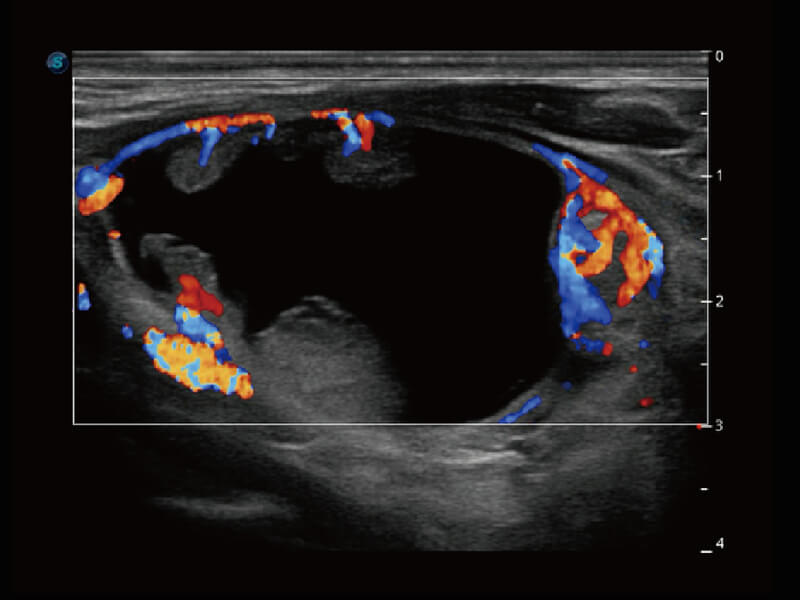

S60探头工艺,从前端信号处理每一个环节采集无损声学数据,真实还原组织原貌,再现解剖细节。

超宽频带技术,为容积成像带来优质的二维图像基础,为您呈现丰富的结构细节,栩栩如生地展示宝宝的宫内形态以及各种组织的立体结构。